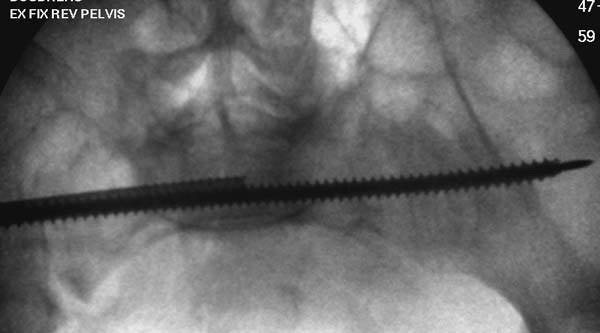

Здесь снимки, которые показывают направление стержня, а также идею

репозиции вытяжением. На рентгенопроницаемых столах имеется возможность

установить дополнительную раму, где по желанию можно увеличить или

уменьшить высоту угла вытяжения. Для репозиции таза больной в положение

на спине, стержень для вытяжения остается во время операции. Система

подойдет для тракции головки бедра из вертлужной впадины, и для этого

стерильная веревка и Synthes Universal Chuck with T-Handle.

Двухстороннее повреждение крестца и травматическая ампутация бедра, где

неопытной бригадой дежурантов установлен верхний наружный фиксатор для

стабилизации. На третий день ревизия на более стабильный, и

окончательная фиксация. Первые снимки после стабилизации таза, и другие,

где показаны (параллельные) правильная установка на AIIS т.е на месте

прикрепления прямой мышцы бедра. Ампутация закончена костно пластическим

методом.